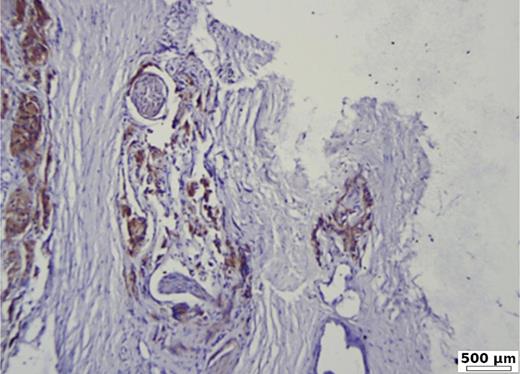

Fig. 4.

Strong BSP expression of 90% in poorly differentiated prostate carcinoma (G3, ISUP 5), with capsular and perineural invasion. Immunohistochemistry BSP.

Fig. 5.

Low BSP expression (20%) in a moderate differentiated acinar prostate carcinoma (G2, ISUP 2). Immunohistochemistry BSP.